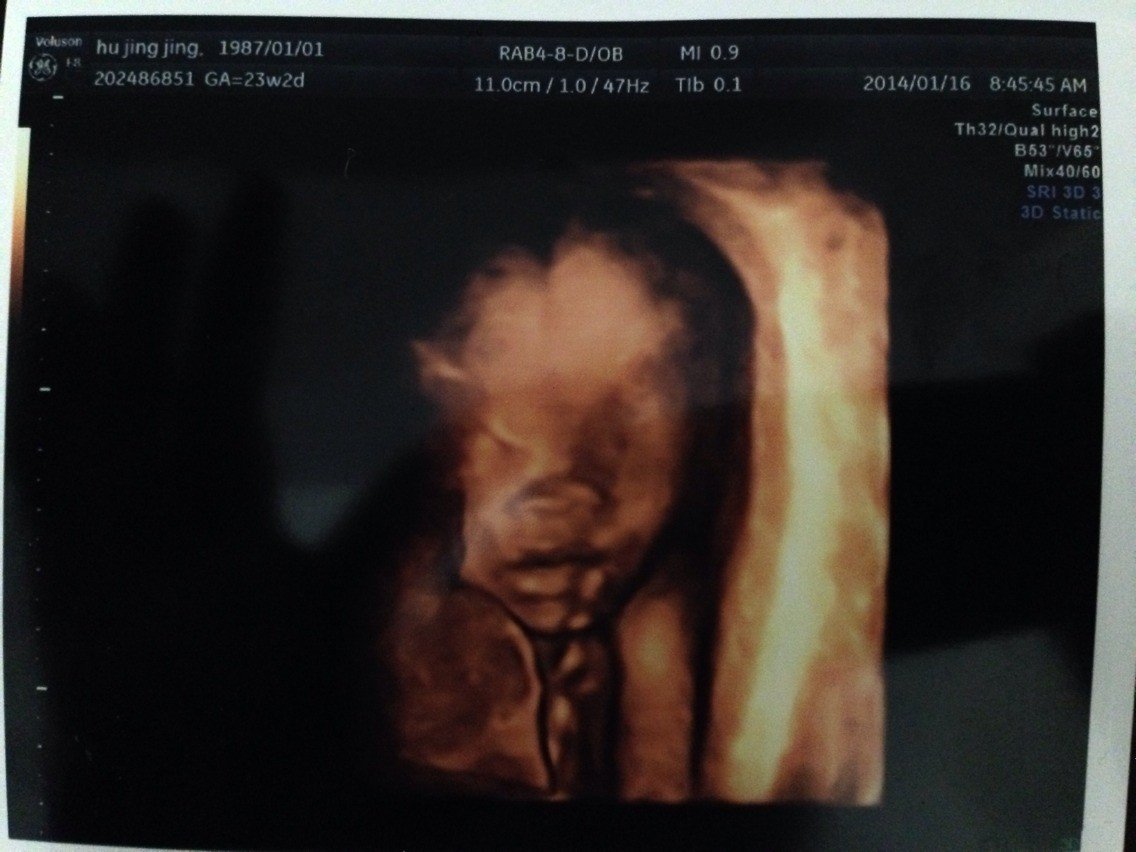

你好,怀孕23W2D,做了四维彩超,想知道是男孩女孩哦,嘿嘿,谢谢了… 点击展开 匿名用户 2014-01-16 14:49 为您推荐: 其他回答 脸到像爸爸的,不过不知道是男还是女, 扬志明_XJAc 2014-01-20 20:52 这个是看不出来的,得医生跟你说 匿名用户 2014-01-17 09:58 相关问题 做四维彩超可以干嘛?能看出来男孩女孩吗? 大夫你好!怀孕6周做那些检查 你好,我怀孕23周做彩超小孩570克重,正常吗??